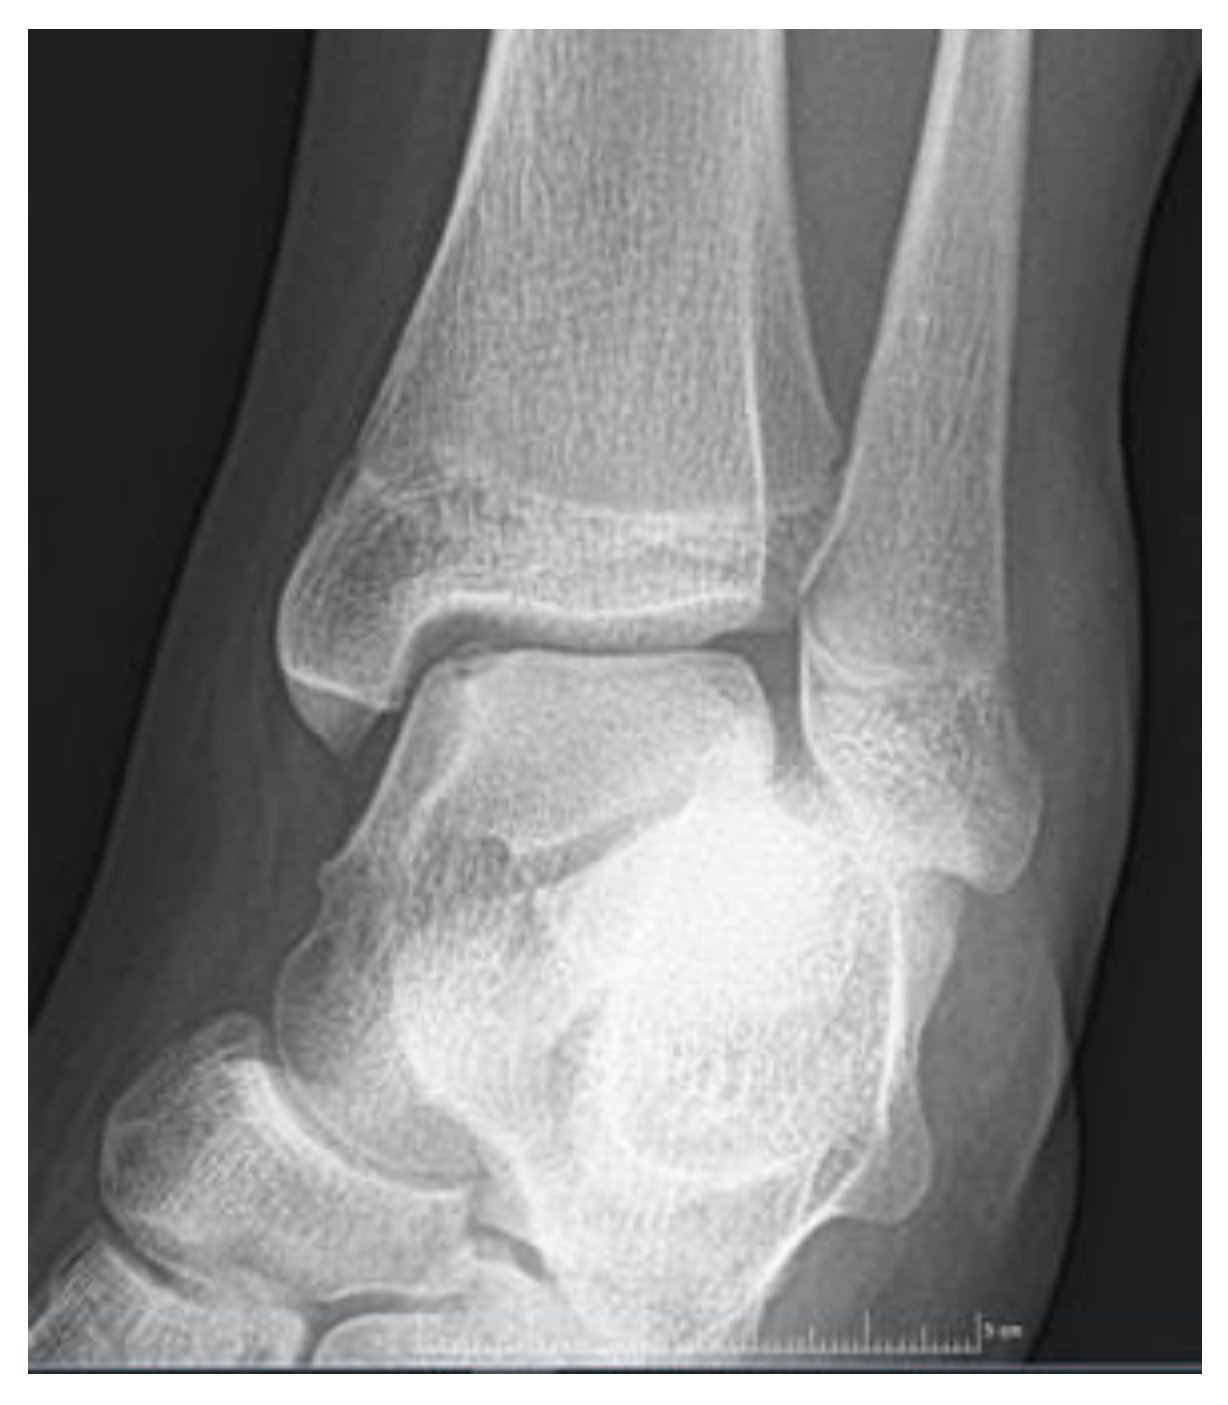

| Stage 2 | Partially detached osteochondral fragment | A lesion with signs of early separation | Lesions with partial discontinuity which are stable when probed | Articular cartilage has been breached with a low signal rim behind the fragment indicating fibrous attachment | OSteochondral fragment with clear margins, without fluid in between | Epiphyseal cartilage lesion with complete or incomplete rim calcification |

| Stage 3 | Completely detached, non-displaced | Partially detached lesion | Lesions with complete discontinuity which are not dislocated (Dead in situ) | High signal changes behind the fragment indicate synovial fluid between the fragment and the underlying subchondral bone | Fluid is visible partially between the fragment and bone | Partially or completely ossified lesion |

| Stage 4 | Completely detached and displaced - loose body | Craters with loose bodies (salvageable or non-salvageable) | Empty defect bed with loose or dislocated fragment | Loose body | Fluid surrounds the fragment but it is still in situ | A healed osseous lesion with scar |

| Stage 5 | Scranton and McDermott modification : Subchondral Cyst | - | - | - | The fragment is completely detached and displaced | Unhealed, detached osseous lesion (Sequestrum) |